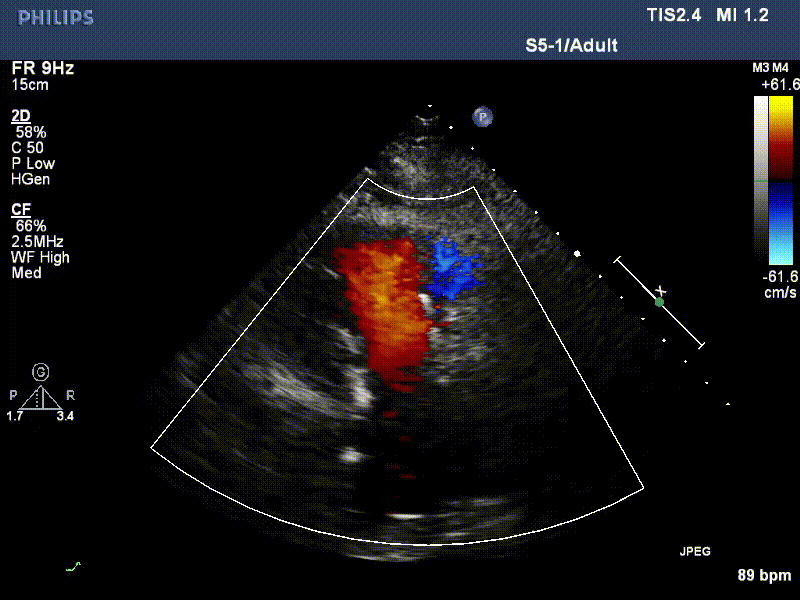

流并分別伴有房顫和房撲,高外科手術風險。術前超聲提示,兩例患者下腔靜脈寬度分別為13mm和29mm,右房內徑(上下徑和左右徑)分別為52×41mm和53×43mm,彩色多普勒顯示極重度三尖瓣反流,VCW分別為14×15mm和10mm。

1年前,兩例患者因難治性雙下肢水腫輾轉多家醫院尋求救治,考慮到兩例患者高齡、基礎疾病多、STS評分高,不適合傳統外科開胸手術,葛均波院士及其團隊周達新教授、潘文志教授、張源博士、陳莎莎博士、陳丹丹博士聯合心外科王春生、魏來主任,麻醉科繆長虹、郭克芳主任以及心超室的潘翠珍教授、李偉教授共同討論決定,采用我國創新器械LuX-Valve Plus經血管三尖瓣置換系統為患者進行手術。相較于第一代產品LuX-Valve,LuX-Valve Plus經血管三尖瓣置換系統對輸送系統進行了全面升級,實現了經頸靜脈入路的方式,進一步減小了手術風險和對患者的創傷。目前隨訪1年心超結果顯示,三尖瓣極重度反流消失,人工三尖瓣瓣膜穩定牢固,瓣葉活動度良好,右心室及下腔靜脈明顯縮小,心輸出量增加。兩位老人手術后沒有出現過胸悶氣促的癥狀,下肢水腫緩解,活動耐力提升,生活質量也大為提高。

圖2 患者植入LuX-Valve Plus后,1年隨訪心超提示無三尖瓣反流